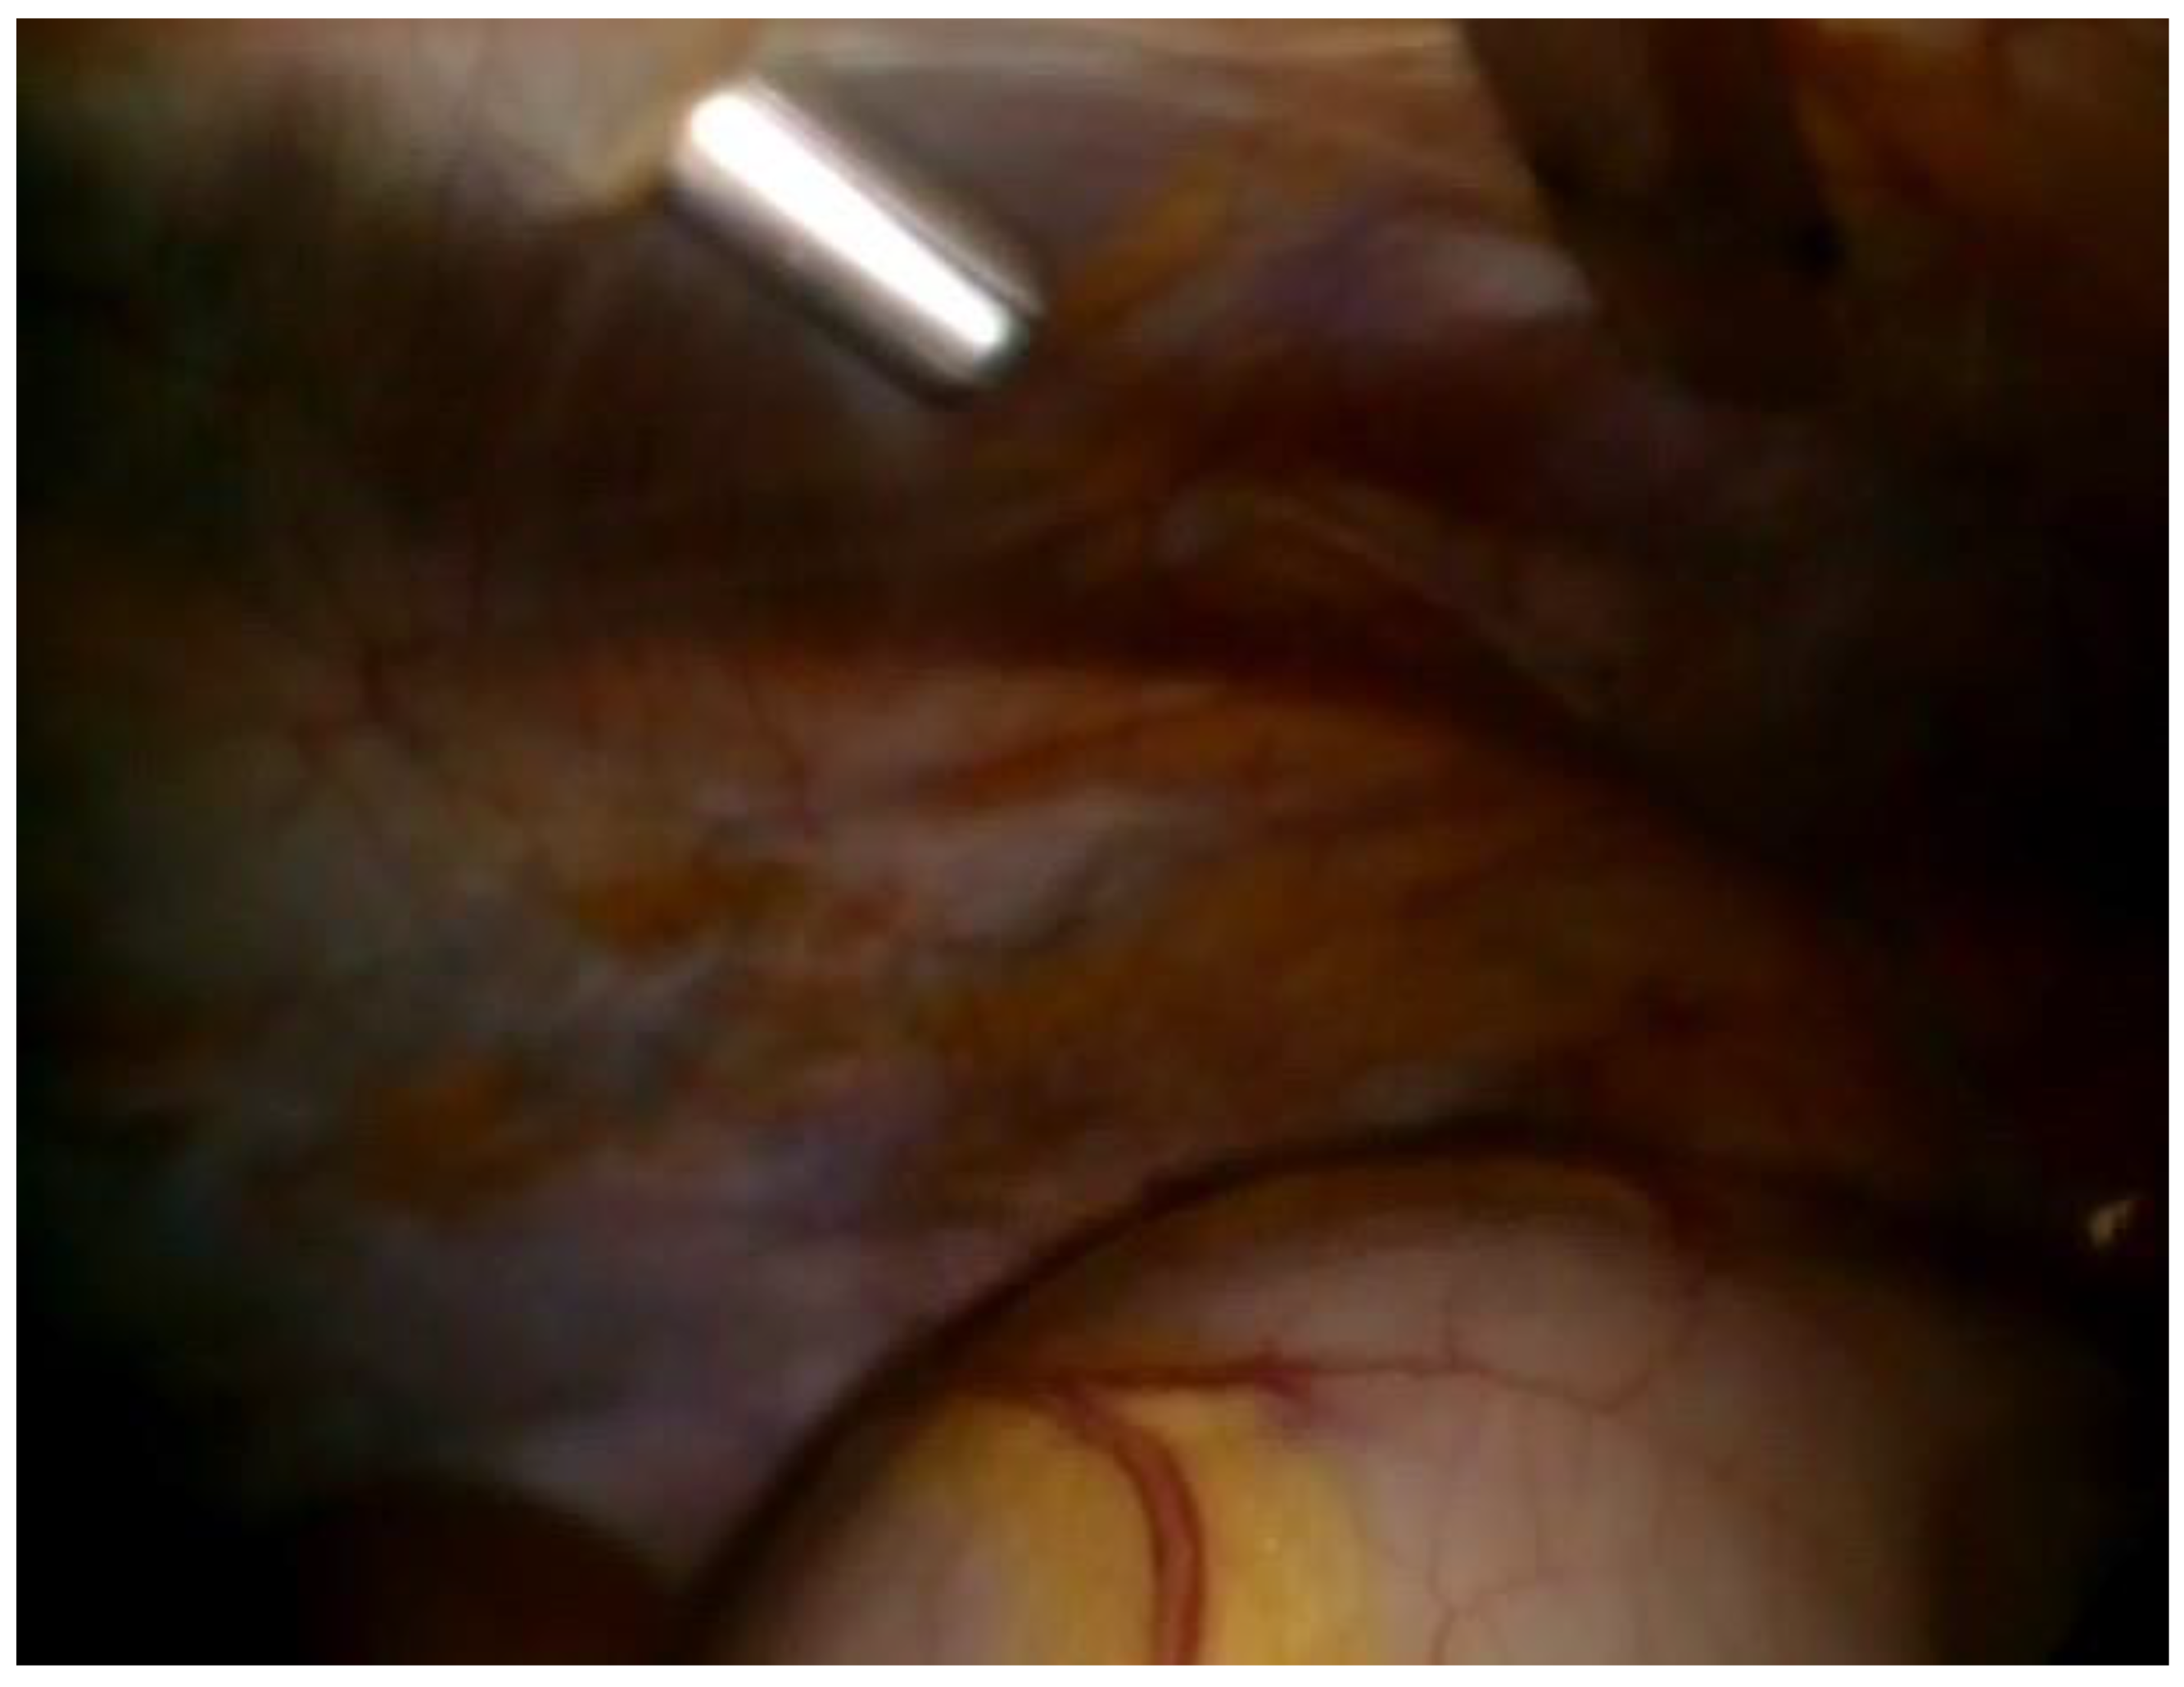

Figure 4.

Skin labelling of the thickest part of the rectus abdominis muscle and the course of the inferior epigastric artery.

In all candidates for peritoneal dialysis (PD), a laparoscopic insertion of PDC under general anesthesia has been performed in our institution for the past 15 years. Recently, we implemented a modified technique with intraoperative US evaluation of the abdominal wall on the side of PDC insertion. The abdominal surgeon performs all PDC insertions under general anesthesia, while the nephrologist joins the surgery to perform an US of the abdominal wall. The side of PDC is agreed upon with patients preoperatively after obtaining informed consent. The patient is placed supine, and a single preoperative antibiotic prophylaxis with 1 g to 2 g cefazolin is given 30 min before the skin incision. If a penicillin allergy is known, patients get 500 mg of vancomycin. The sterile operative field is prepared per standard protocol. Thereafter, the position of the internal cuff and a skin exit site are marked. The coiled Tenckhoff catheters with two dacron cuffs and a special trocar are used for rectus sheath tunneling. When the procedure is commenced, an US evaluation of the abdominal wall is performed ipsilaterally to the PDS insertion into the abdominal cavity. (Figure 1). The rectus abdominis muscle width is measured with the US (Figure 2), and the course of the inferior epigastric artery is determined with colored US Doppler (Figure 3). On the abdominal wall, the thickest part of the rectus abdominis muscle and the course of the inferior epigastric artery are both marked with a pencil (Figure 4). After that, the position of the internal cuff is determined 2–3 cm laterally from the umbilicus, where the rectus muscle is sufficiently thick. The positions of the external cuff and the skin exit site are also marked on the skin before insertion. After the US evaluation of the abdominal wall is completed, the laparoscopic insertion of PDC is performed. A standard laparoscopy is performed with one 5 mm trocar above the umbilicus and a 5 mm 30-degree camera. The second 5 mm trocar is inserted laterally as a working trocar for a laparoscopic grasper. The 5 mm skin incision is initially performed above the umbilicus, and a Veress needle is blindly introduced into the abdominal cavity. Aspiration and a water drop test is performed to ensure that the Veress needle is properly inside the peritoneal cavity. Pneumoperitoneum is created with CO2, and the intraabdominal pressure is maintained around 12 mm Hg, as in standard laparoscopy. A 5 mm trocar is blindly introduced into the abdominal cavity at this site. Although all patients have preoperative abdominal US performed, we further perform diagnostic laparoscopy with a 5 mm 30-degree camera to exclude any other associated intraabdominal pathology. Contralateral to the PDC insertion, another 5 mm trocar is inserted under laparoscopic vision and a camera is moved to that trocar so that the entry site of the catheter into the peritoneal cavity can be visualized during insertion. The patient is tilted to a slight Trendelenburg position, thus allowing a better exposure of the deep pelvis, which is the point for inserting the PDC tip. The Trendelenburg position enables the small bowel loops to retreat from the pelvis so that the pelvis can be further inspected for possible adhesion. The advantage of laparoscopy is also to enable advanced laparoscopic procedures, such as adhesiolysis if needed. Thereafter, the 1 cm skin incision is performed ipsilateral to the side of PDC placement, and a special trocar is used for rectus sheath tunneling. Because of the preoperative US evaluation of the abdominal wall, we are aware of the inferior epigastric artery course, so we can accommodate the rectus sheath tunneling course so as to avoid vessel injury and bleeding. Rectus sheath tunneling is performed with a special trocar, through which the PDC is then inserted into the abdominal cavity. The trocar is introduced under a 45-degree angle through a small skin incision into the subcutaneous tissue and is then blindly forwarded through the abdominal wall (Figure 5 and Figure 6). The peritoneum is penetrated under direct laparoscopic vision to avoid any bowel or large vessel injury. The PDC is introduced through the trocar into the abdominal cavity, and the trocar is removed. With an atraumatic laparoscopic grasper, the coiled tip of the PDC is placed into the deep pelvis and the inner cuff is placed preperitoneally under direct laparoscopic supervision. The PDC is exteriorized laterally, and the outer cuff is placed in the subcutaneous tissue. The distance between the outer cuff and the skin exit site should be 2–4 cm. At the end of the laparoscopy, the proper position of the PDC tip and potential bleeding from the peritoneum at the trocar and PDC breakthrough sites are rechecked, respectively. All trocars and working instruments are removed from the abdominal cavity, and the pneumoperitoneum is released. The PDC is flushed with 50 mL of normal sterile saline to ensure the fluid flows freely in and out of the abdominal cavity. The fascia at trocar sites is sutured, and skin incisions are sutured with 4/0 absorbable sutures. The latter are infiltrated with a local anesthetic. When the surgical part of the PDC insertion is completed, an US is performed again to check for a proper position of the PDC tip and inner cuff. The outer end of the PDC is connected to the titanium adapter and transfer set. The complete outer part of the PDC is covered with gauze and transparent dressing. Following the procedure, the patient is admitted to the nephrology department, where a small volume flushing (200–500 mL) is started the next day. According to our institutional protocol, after laparoscopic insertion of the PDC, all patients have to wait 4–6 weeks before a full PD is commenced to achieve full healing of both the skin and abdominal wall wounds at trocar sites, thereby preventing (or minimizing) the possible leak. The patient is advised to avoid heavy lifting and strenuous physical activity for 4–6 weeks after the procedure.